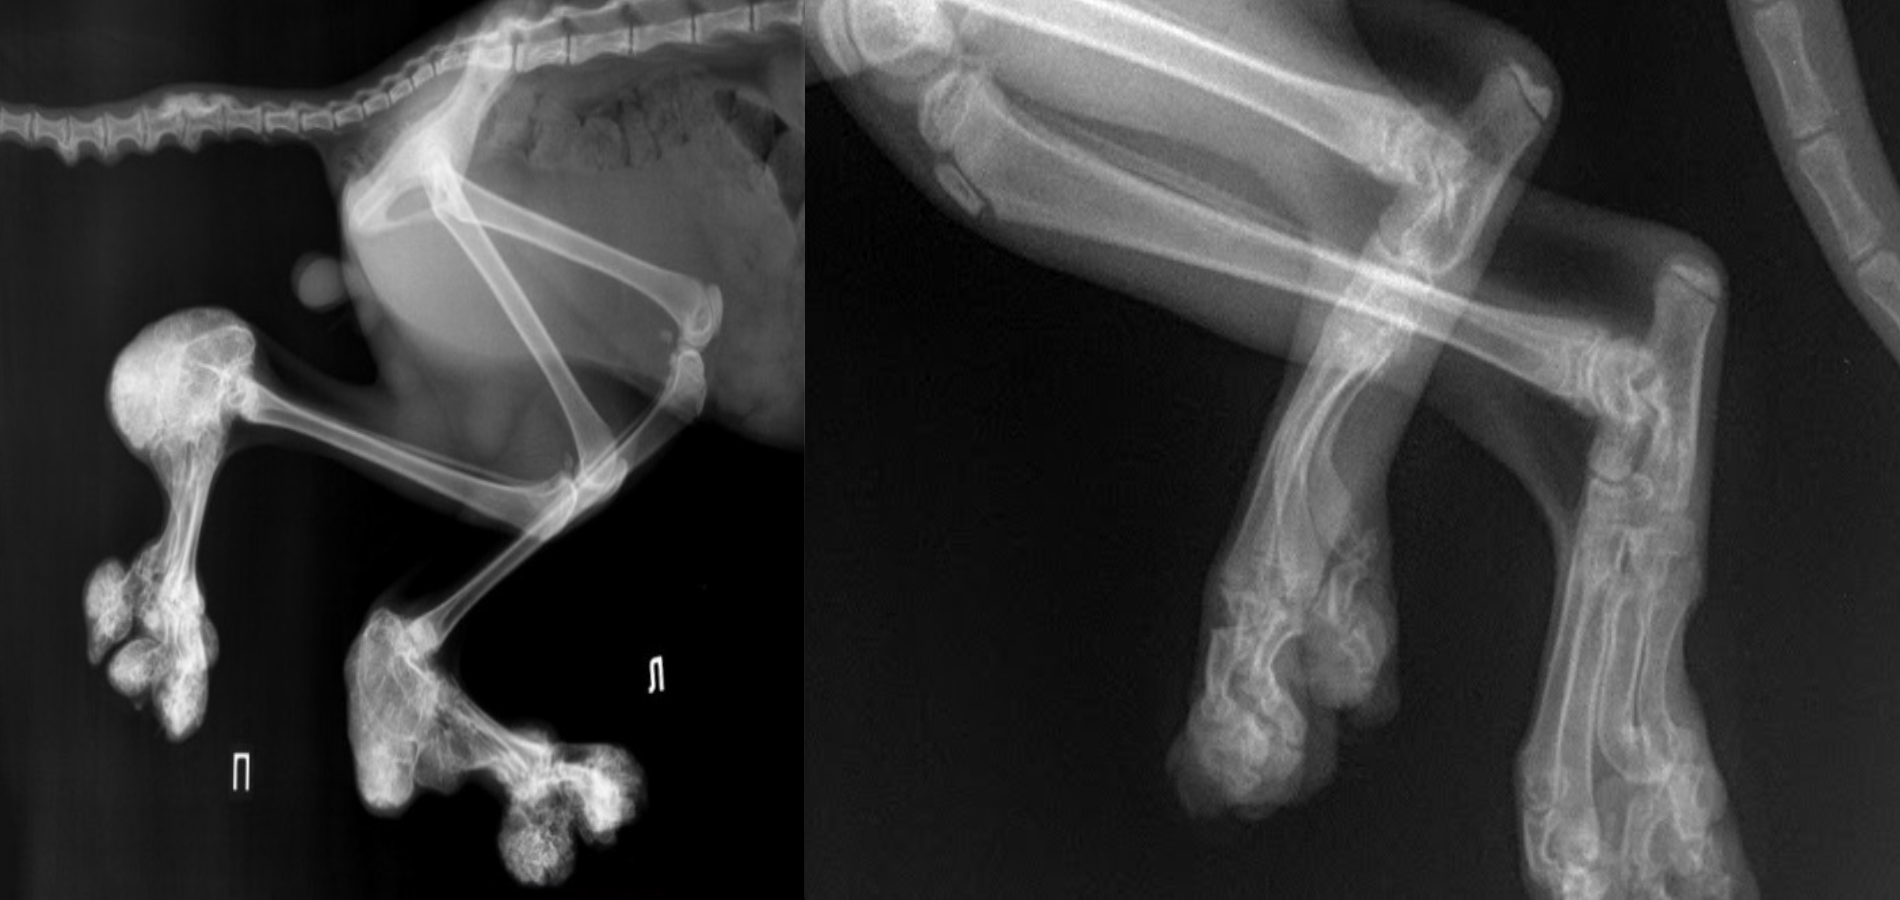

Со временем состояние может ухудшаться: развивается остеоартрит, появляются костные разрастания (экзостозы), что значительно снижает качество жизни питомца.

1. Рентген – выявляет деформации костей, суставов, экзостозы.